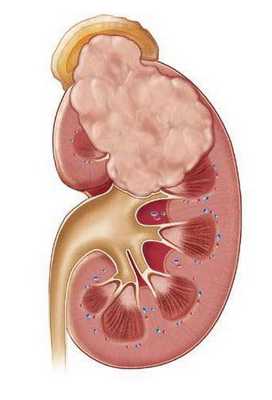

Каждое очередное обострение пиелонефрита сопровождается вовлечением в воспалительный очаговый процесс все новых участков функционирующей почечной паренхимы. В результате вторичного воспаления поверхность почки становится неровной, формируются крупные глубокие сегментарные рубцы, расширяется мочеточник. Чаще процесс локализуется в верхнем сегменте почки.

2. Макроскопические и хирургические признаки:

• Увеличенная почка

• Гнойные абсцессы, визуализируемые на поверхности коркового вещества